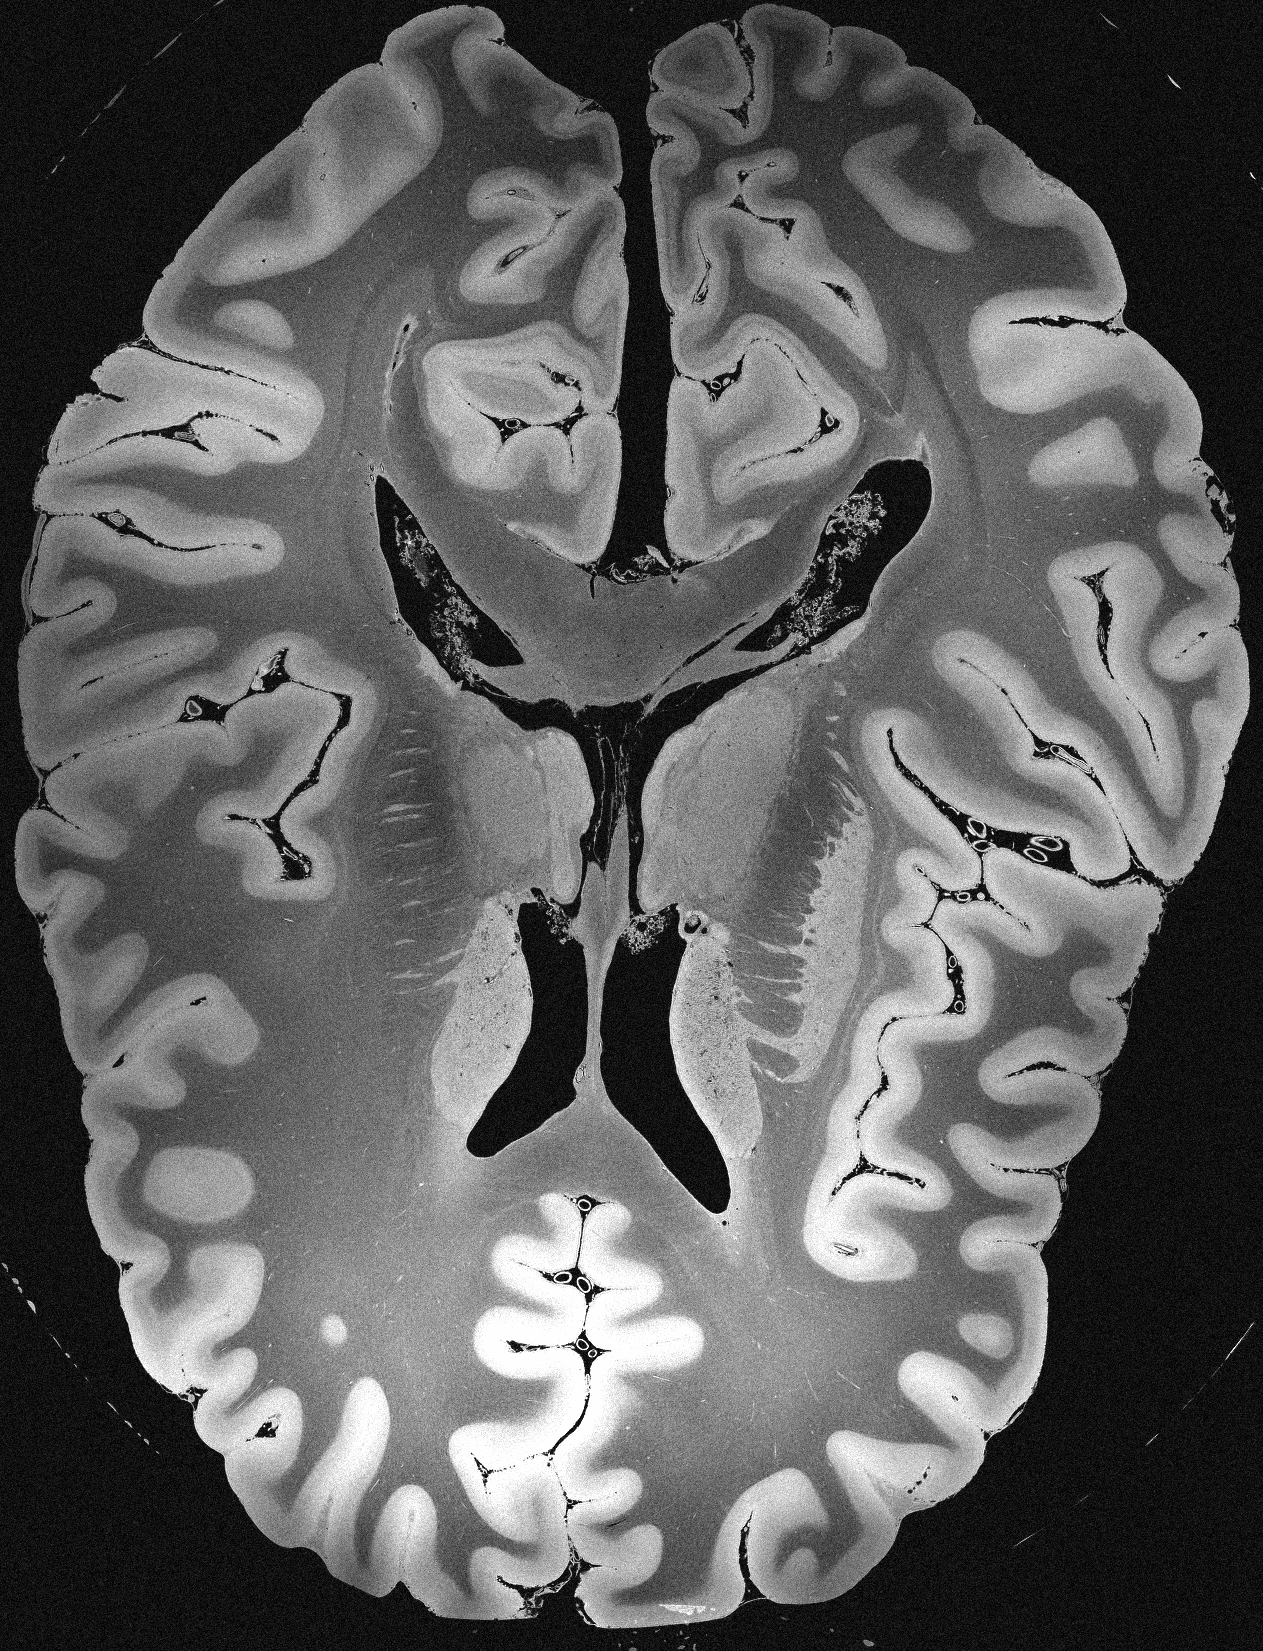

4.2 Registration to a 100 micron ex-vivo brain MRI volume

To showcase the efficacy of our method on real large scale images, we register a 250 in-vivo MRI image (Lüsebrink et al., 2017) to a 100 ex-vivo FLASH human brain volume (Edlow et al., 2019). This represents an inverse problem with more than 11.2B optimizable parameters (compared to 20M for clinical datasets), or 44.8GB of GPU memory. The entire problem does not fit on most GPUs, necessitating distributed multimodal registration. We optimize a composite transform - affine followed by a diffeomorphic mapping; details can be found in Section E.1. Multimodal deformable registration took 58 seconds on 8 NVIDIA A6000 GPUs, which is unprecedented at this resolution. Fig. 6 shows qualitative results, highlighting the ability to register highly detailed structures such as cerebellar white matter; these structures are not visible at macroscopic scales. The resultant advantages of performing registration at this scale can allow researchers to characterize the neuroanatomy at microscopic resolutions and allow morphometric analysis of cortical layers and subcortical nuclei among other structures.